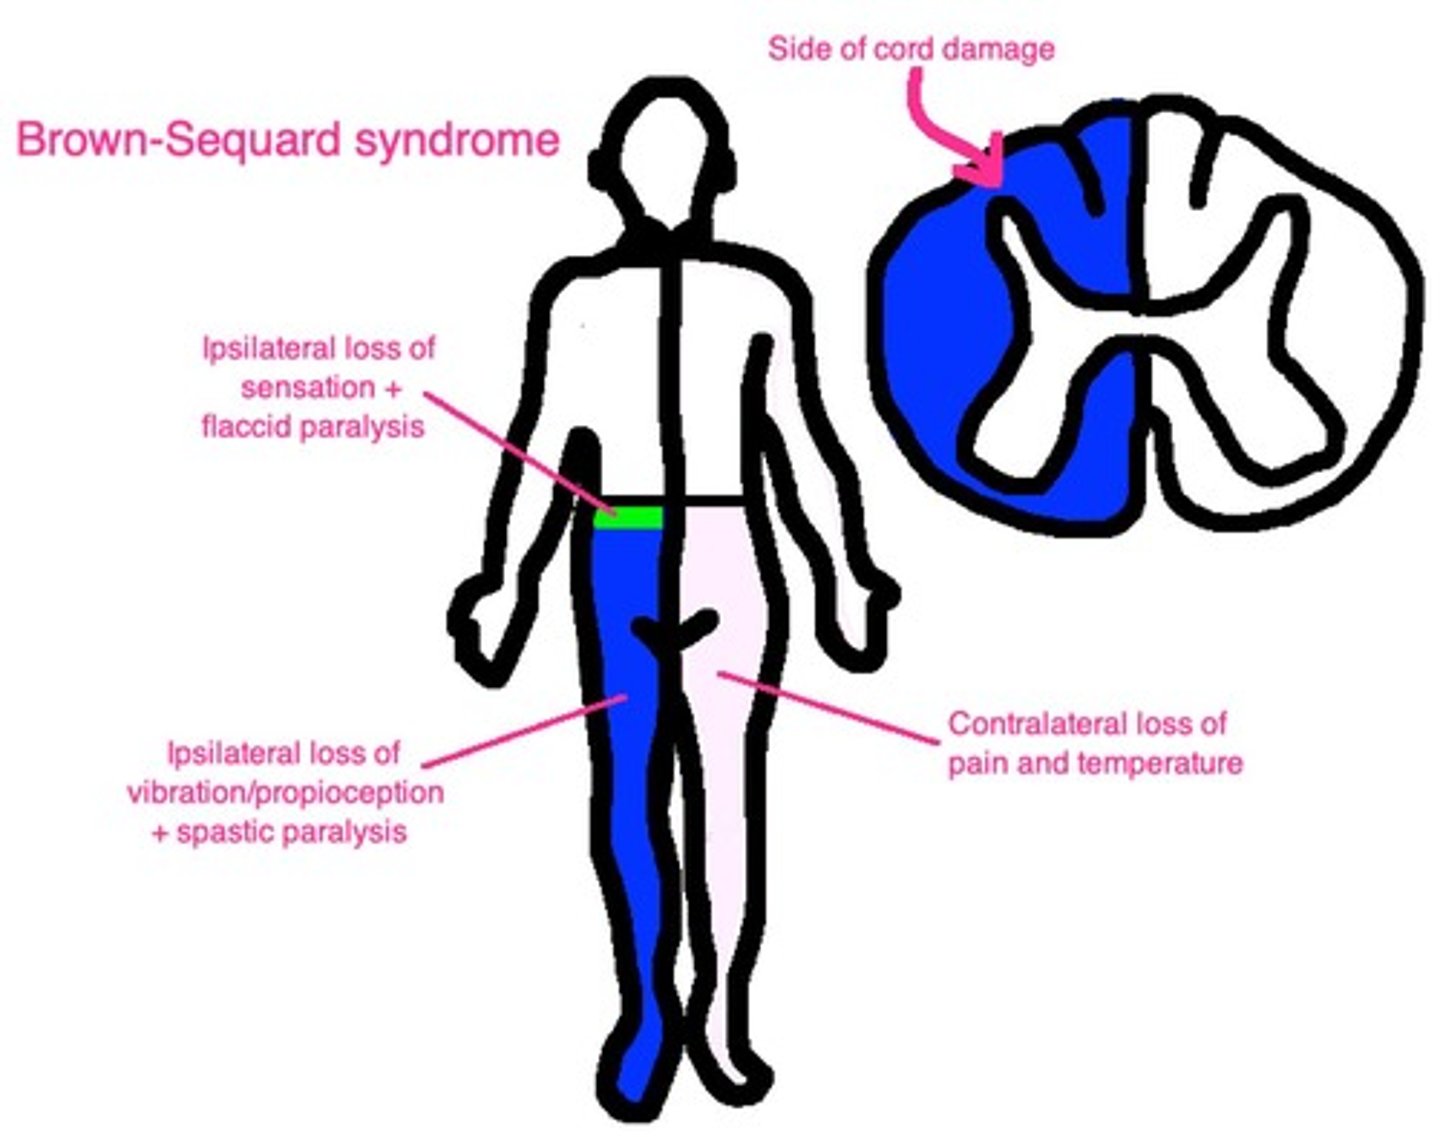

Pain and temperature sensation from contralateral body.

Decussation point

Cross-over (decussation) point is in spinal cord, meaning if, e.g., the left spinothalamic tract is damaged, we lose pain and temperature on the right side of the body below the lesion.

Corticospinal tract

Motor function from ipsilateral body.

Dorsal columns

Carry vibration + proprioception from ipsilateral body.

Brown-Sequard Syndrome

Ipsilateral loss of vibration + proprioception (dorsal columns).

Brown-Sequard Syndrome

Ipsilateral loss of motor function (corticospinal tract).